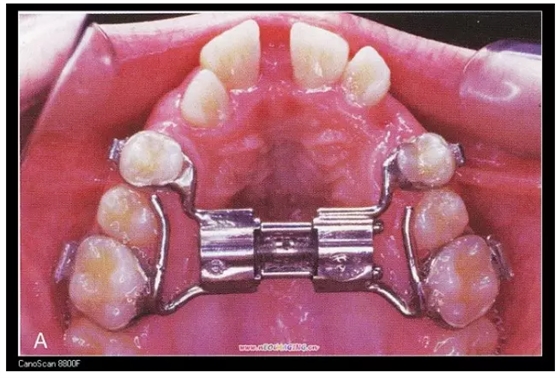

三、擴(kuò)弓器

很多牙列不齊常伴隨牙弓過(guò)窄,所以擴(kuò)弓器是正畸醫(yī)生的好伙伴,它可以以多種形態(tài)和您見面。